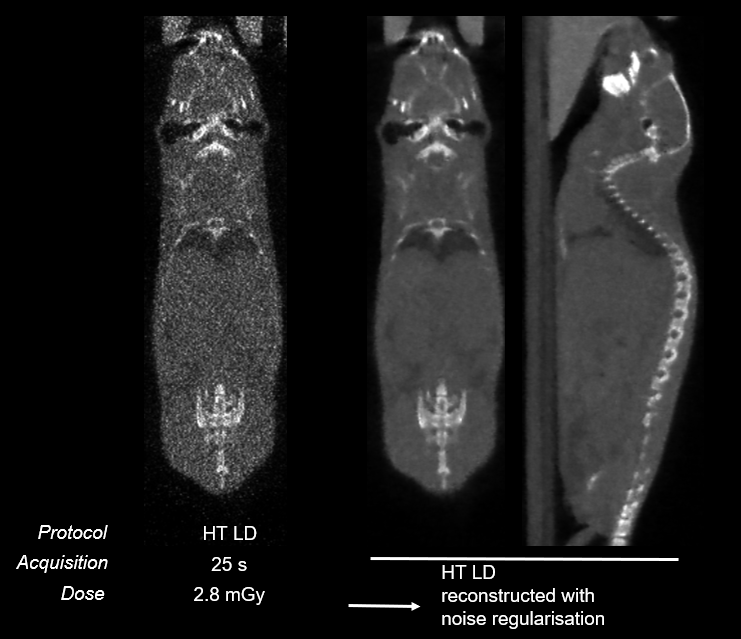

图 15.在噪声调整技术下的极低放射剂量和快速 CT 成像:仅需 2.8mGy 和 25s【2】 。